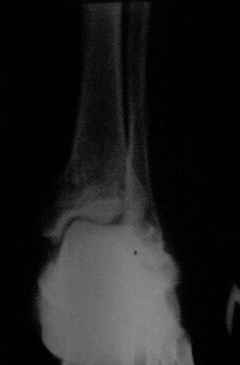

Здравствуйте,коллеги!Все оказалось даже хуже!Сегодня больной госпитализирован и:

С левой стопой дело похуже. Нужен прямой снимок, да и боковой не помешает повторить на всю стопу, ну и плюс аксиальный. Готовтье аппарат.

Отправляю снимки(свежие)и фото стоп.

С уважениемД.Б.